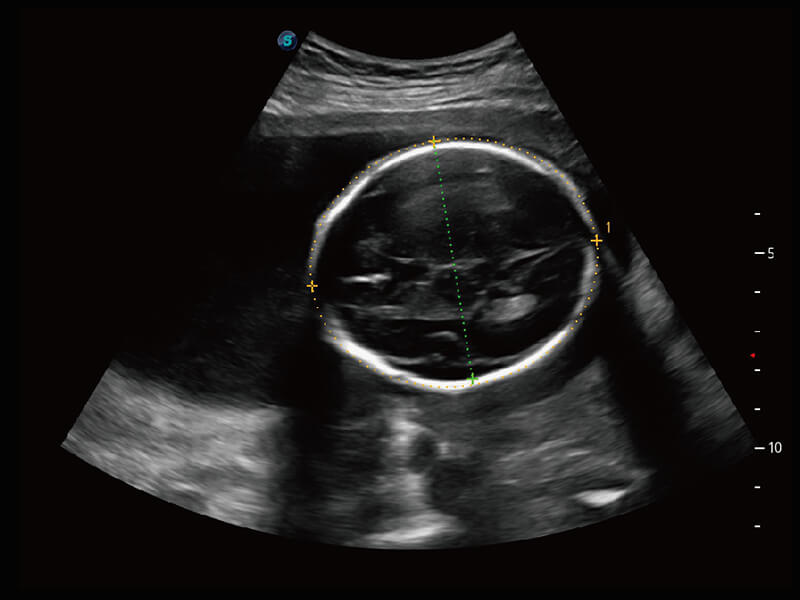

彩色多普勒超声诊断系统

性能优异的硬件架构,极大提升超声系统的运行效率和数据处理能力。相比以往超声成像系统,Wis+平台为您带来极快的响应速度和成像帧频,提升检查流畅度。

S60探头工艺,从前端信号处理每一个环节采集无损声学数据,真实还原组织原貌,再现解剖细节。